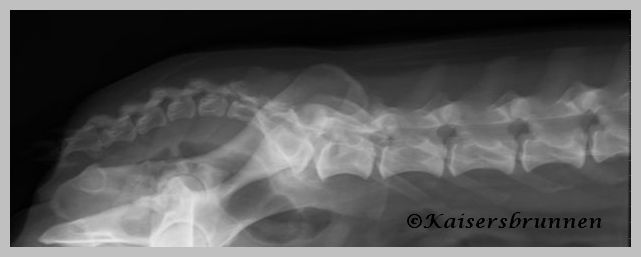

Unten aufgeführten Röntgenbilder sind von meiner Weißen

Schäferhunde Dame Delena,

sie wies auch im hohen Alter von 11 Jahren keinerlei Verkalkungen

oder Veränderungen in der Wirbelsäule sowie im

Hüftbereich auf.